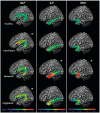

Primary progressive aphasia is a clinical syndrome that encompasses three major phenotypes: non-fluent/agrammatic, semantic and logopenic. These clinical entities have been associated with characteristic patterns of focal grey matter atrophy in left posterior frontoinsular, anterior temporal and left temporoparietal regions, respectively. Recently, network-level dysfunction has been hypothesized but research to date has focused largely on studying grey matter damage. The aim of this study was to assess the integrity of white matter tracts in the different primary progressive aphasia subtypes. We used diffusion tensor imaging in 48 individuals: nine non-fluent, nine semantic, nine logopenic and 21 age-matched controls. Probabilistic tractography was used to identify bilateral inferior longitudinal (anterior, middle, posterior) and uncinate fasciculi (referred to as the ventral pathway); and the superior longitudinal fasciculus segmented into its frontosupramarginal, frontoangular, frontotemporal and temporoparietal components, (referred to as the dorsal pathway). We compared the tracts' mean fractional anisotropy, axial, radial and mean diffusivities for each tract in the different diagnostic categories. The most prominent white matter changes were found in the dorsal pathways in non-fluent patients, in the two ventral pathways and the temporal components of the dorsal pathways in semantic variant, and in the temporoparietal component of the dorsal bundles in logopenic patients. Each of the primary progressive aphasia variants showed different patterns of diffusion tensor metrics alterations: non-fluent patients showed the greatest changes in fractional anisotropy and radial and mean diffusivities; semantic variant patients had severe changes in all metrics; and logopenic patients had the least white matter damage, mainly involving diffusivity, with fractional anisotropy altered only in the temporoparietal component of the dorsal pathway. This study demonstrates that both careful dissection of the main language tracts and consideration of all diffusion tensor metrics are necessary to characterize the white matter changes that occur in the variants of primary progressive aphasia. These results highlight the potential value of diffusion tensor imaging as a new tool in the multimodal diagnostic evaluation of primary progressive aphasia.